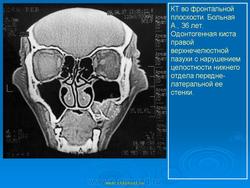

На верхней челюсти кисты встречаются в 2 раза чаще, чем на нижней. Кисты от верхних центральных резцов и клыков могут расти в сторону полости носа — при этом образуется выпячивание в полость нижнего носового хода или под нижнюю носовую раковину (симптом Gerber). Иногда может отмечаться рост в сторону твердого нёба, в этом случае на твердом нёбе появляется полушаровидное вздутие. Если рост кисты происходит в сторону верхнечелюстного синуса, наружных проявлений долгое время не отмечается. Диагноз в этом случае обычно ставится при нагноении кисты, проявлении симптомов периостита и синусита и на основе данных рентгенографии. Также на верхней челюсти может отмечаться рост кисты в сторону преддверия рта, при этом отмечается выбухание и деформация альвеолярного отростка.